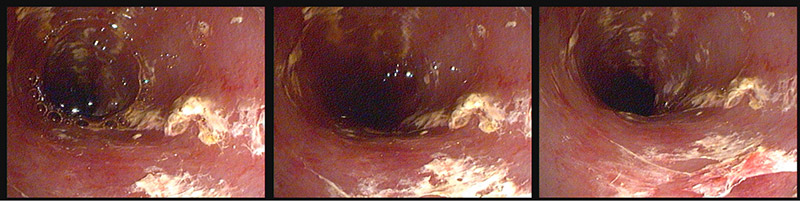

Но в нашем ветеринарном центре есть и второй вариант – гастроскопия, более точное название — эзофагогастродуоденоскопия (ЭГДС). Одна из разновидностей эндоскопического обследования — визуальный осмотр стенок пищевода, желудка и двенадцатиперстной кишки при помощи специального инструмента — видеогастроскопа, вводимого в желудок через ротовую полость и пищевод под общим наркозом.

В ходе получасового исследования (гастроскопии) Роки был поставлен диагноз острый дуоденит (воспаление двадцативёрстной кишки). Питомцу было назначено симптоматическое лечение, а также диетическое кормление. Роки идет на поправку.